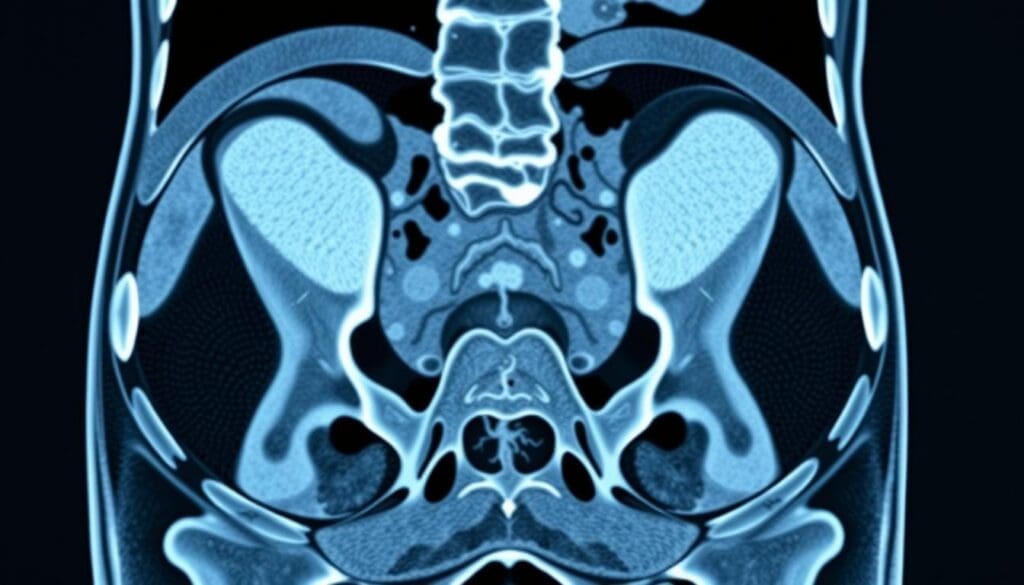

At Liv Hospital, we know how key it is to accurately find inguinal hernias for the best care. Advanced imaging is vital for precise diagnoses and top-notch service. CT scans are a key tool, showing detailed views of the body’s structures. This is key for treatment planning.

How CT Scans Work for Hernia Detection

CT scans are key in finding inguinal hernias. They use X-ray technology to show the body’s inside. This helps see the small details of the inguinal area and spot hernias.

Basic Principles of CT Imaging

CT scans mix X-rays and computer tech for detailed body images. The patient lies on a table that moves into a scanner. The scanner spins around, taking X-ray pictures from many angles.

These pictures are then put together into slices. This gives a full view of the body’s inside.

It’s important for CT scans to tell different tissues apart. Contrast agents help by making certain parts stand out more. They can be taken by mouth or through an IV.

Specific Protocols for Hernia Evaluation

For finding hernias, special CT scan rules are followed. These rules help make the images clearer and more accurate. The Valsalva maneuver is often used. It’s when the patient tries to push air out with their mouth closed and nose pinched.

This makes it easier to see hernias. Thin-section imaging and multiplanar reconstructions also help. They let doctors see the inguinal canal and nearby areas well.

This helps them find hernias, know their size, and where they are. It also helps figure out any problems they might cause.

Understanding how CT scans work and their special rules for hernias shows their importance. They are a strong tool for finding inguinal hernias and helping decide how to treat them.